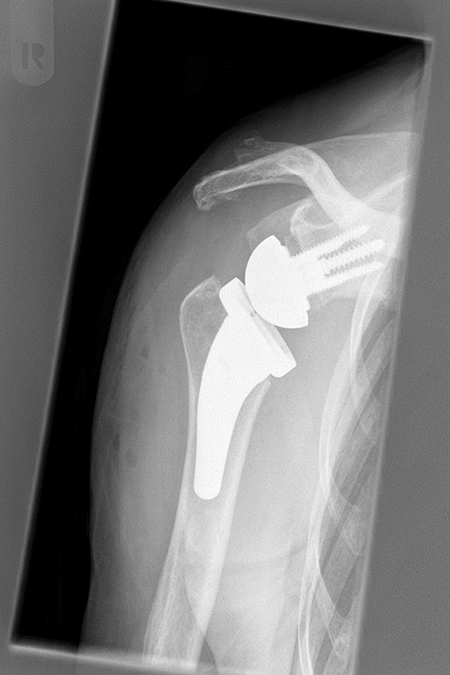

• Künstliches Schultergelenk

Bei fortgeschrittenem Sehnendefekt kommt es zum Höhertreten des Oberarmkopfes unter das Schulterdach. Die dauerhafte Dezentrierung führt zu einem speziellen Bild des Gelenkverschleißes (Defektarthropathie). In solchen Fällen können künstliche Schultergelenke sehr hilfreich eingesetzt werden.

Einen Lösungsansatz stellt die inverse Prothese dar. Durch die besondere Bauart dieses künstlichen Schultergelenks wird das Drehzentrum des Oberarmkopfs zur Seite und nach unten verschoben. Hierdurch erhält der Schulterkappenmuskel (M. deltoideus) einen erheblich besseren Hebelarm, was einerseits zu einer deutlichen Schmerzreduktion, andererseits zu einer adäquaten Schultergelenksfunktion führt. Der Erfolg eines solchen künstlichen Gelenkes basiert einerseits auf einer Gelenkrekonstruktion, die das entsprechende Abnutzungsmuster des Gelenkes berücksichtigt (Farvard-Klassifikation), zum anderen auf einer gut funktionsfähigen Schultermuskulatur soweit diese noch intakt ist. Dabei kommt der möglichst noch vorhanden außendrehenden Muskulatur des Muskulus Infraspinatus und Teres minor (Schultermuskeln) neben dem Schulterkappenmuskel (m. deltoideus) eine besondere Bedeutung zu.

Fortgeschrittene Omarthrose mit obenliegendem Substanzverlust an der knöchernen Pfanne (E3 Glenoid nach Farvard) bei einer Patientin mit Polyarthrose. Zementfreie Implantation einer Kurzschaft Inversen Schulterendprothese 2020 mit knöchernem Aufbau des Defektes aus dem eigenen Oberarmkopf (BIO RSA).  Sehr gutes Ergebnis nach ca. 6 Monaten.

Kurzschaftendoprothese mit Defektaufbau Glenoid (BIO RSA)